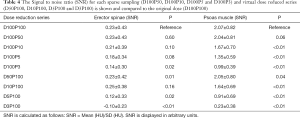

The Signal-to-noise ratio (SNR) for each virtually tube reduced series is shown in Table 4. In the erector spinae the SNR did not reveal significant differences for the sparse sampling series down to 5% (D100P5) of the original dose (P=0.08). A high ICC was given between the two readers in both muscle compartments (ICC =0.98, P<0.01).